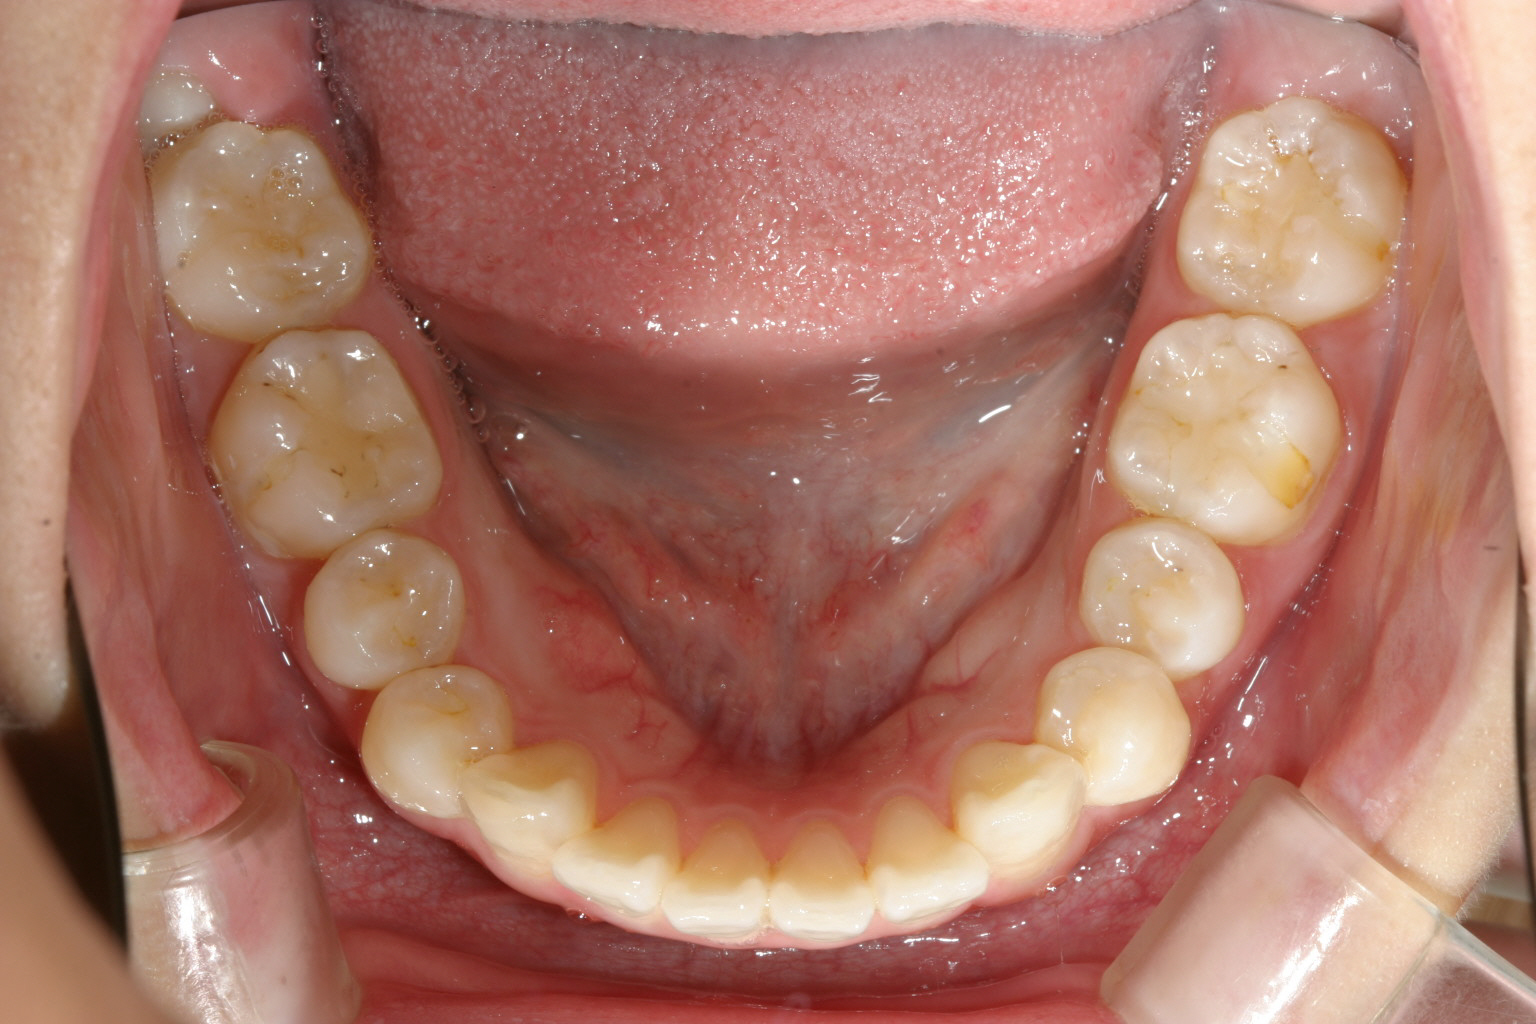

下の歯並びは矯正治療終わったかのように綺麗ですね~

下顎は元々綺麗ですからあまり変化は無いです。